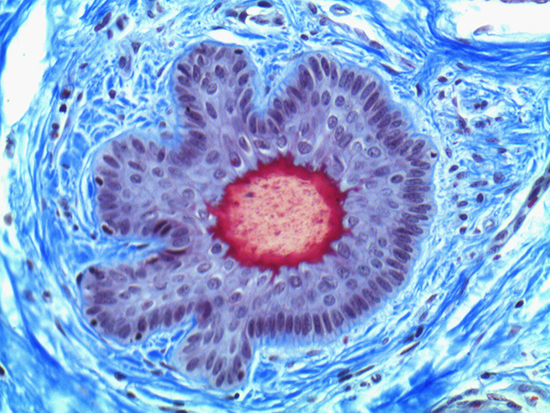

Masson's trichrome stain is incredibly effective in differentiating cells and their components from the surrounding connective tissues. One of the most common stain types, which has been used on the dermal tissue sample seen in the images within this article, yields a number of colors where cell nuclei appear dark red, collagen and other tissues appear green or blue, and cell cylasm appear red/purple (Jones, 2010). These stains have been imaged under brightfield and darkfield illumination, and then again with specific filters to selectively focus on the cellular constituents of the epidermis. The primary application for the epidermal trichrome stains is differentiating healthy collagen and muscles from connective tissues onset with tumorigenesis. Typically the tumors proliferate from muscle cells and fibroblasts deep in the dermal tissue (Blitterswijk, 2010).

Figure 1: Brightfield Image of Dermal Tissue

When comparing Figures 1 and 2, the visual differences are significant. A brightfield image is formed with the illumination source below the sample, and then transmitted light propagates through the sample to the sensor forming a bright, white background with sharp color. A darkfield image is formed by directing light at an oblique angle through the sample, forming a hollow cone of light which is collected by the objective. Darkfield illumination typically yields a dark background with sharp color, but in the case of Figure 2, the collagen and muscle fibers interfered with the light path and caused a blur of light and color. The dark background is hardly evident and only two distinct colors are visible. When analyzing histological stains, brightfield illumination is the preferred technique for lighting a sample.